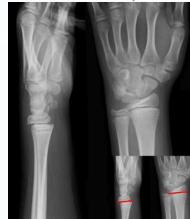

Injury films

Injured and uninjured wrists after premature physeal closure

Asymmetrical Physeal Affection

- Seen on x-ray

- One side grows more than the other

- Causing an increasing deformity

- Oblique Park-Harris growth arrest/recovery line (white arrows)